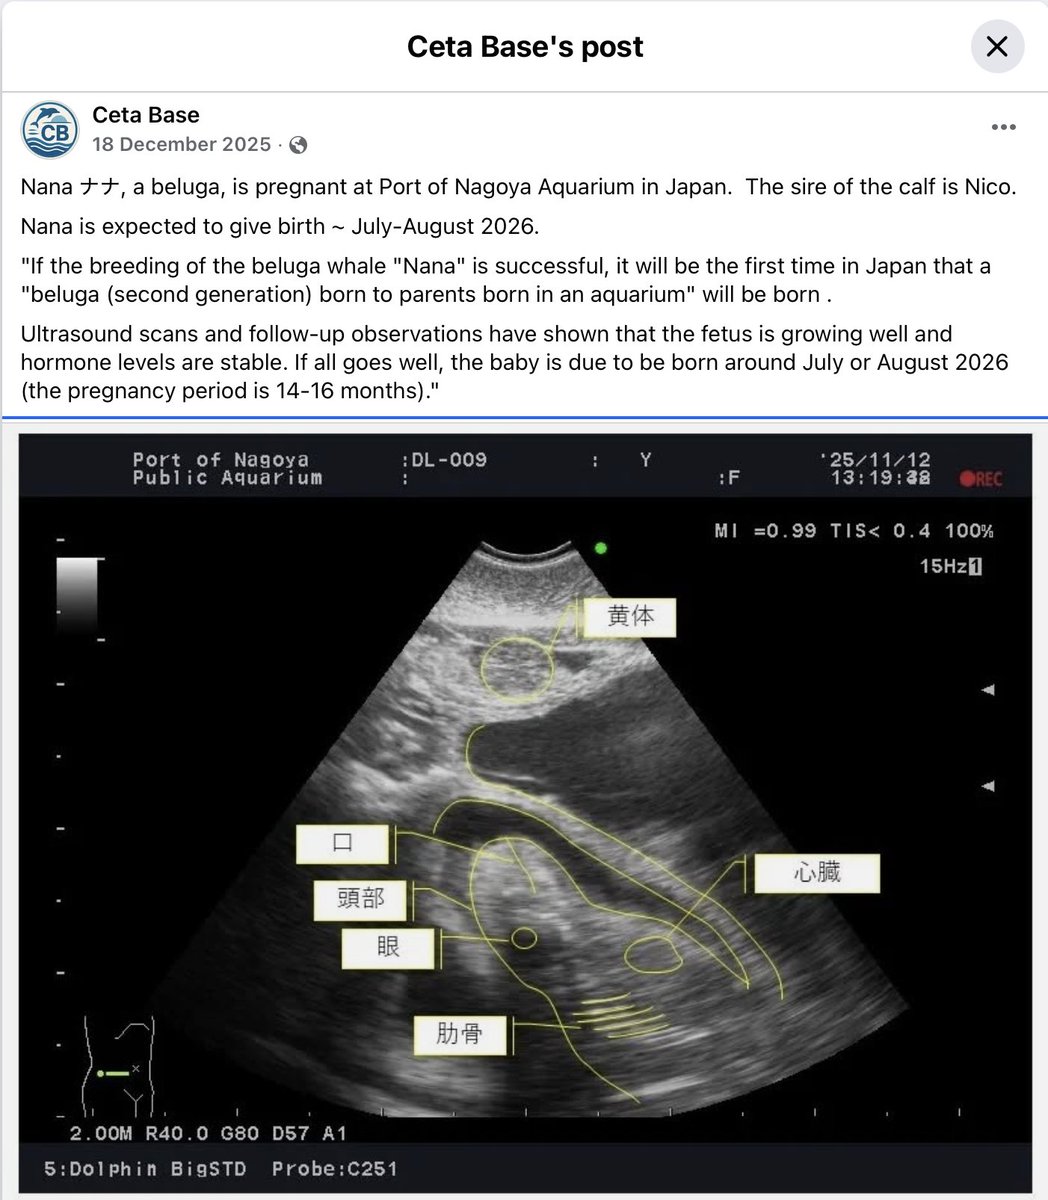

650K ATH! This is just the beginning for $NANA If you didn't already know - Nanaナナ is pregnant and due to deliver sometime between July - August 2026 This is huge. This is more than a 1m runner, we're headed for the moon with Nana🚀🌕🐬

Meet $Nana, the viral beluga whale from Japan. She recently blew up on X, getting tens of millions of views in less than 24 hours. This is the next big animal runner. Creator rewards are used to maximize growth. Website: https://t.co/2B5OCHFT5L https://t.co/c6AUrYnZYr

$NANA is the memecoin of the viral beluga whale from Nagoya Aquarium, Japan. Buy on Pump.fun!